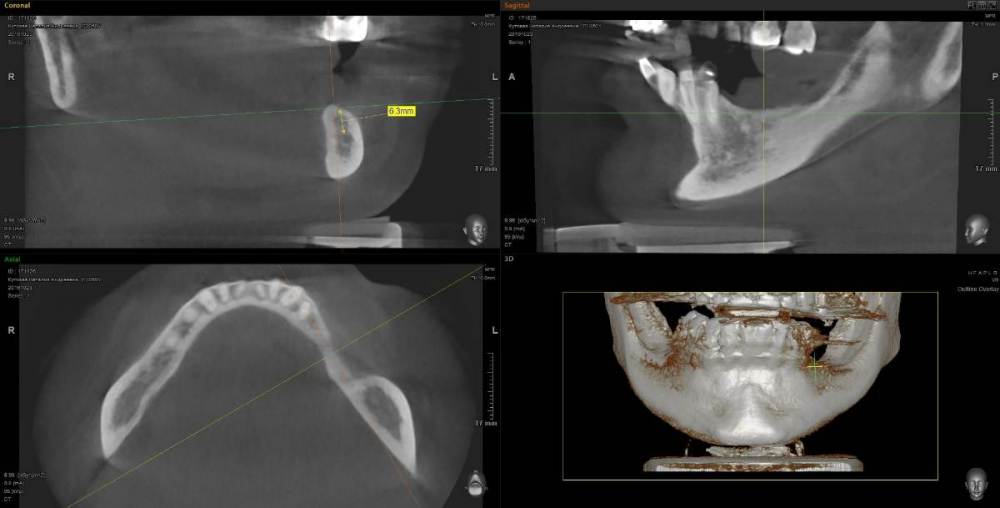

Kostoprav Опубликовано 11 мая, 2021 Поделиться Опубликовано 11 мая, 2021 (изменено) 70%ауто+30% ксено, мембрана цитофлекс, винты самосверлящие после пластики до установки имплантов прошло 8 мес. Изменено 11 мая, 2021 пользователем Kostoprav 3 6 Ссылка на комментарий

Карен Аванесов Опубликовано 12 мая, 2021 Поделиться Опубликовано 12 мая, 2021 20 часов назад, Kostoprav сказал: 70%ауто+30% ксено, мембрана цитофлекс, винты самосверлящие после пластики до установки имплантов прошло 8 мес. Замечательно! 1 Ссылка на комментарий